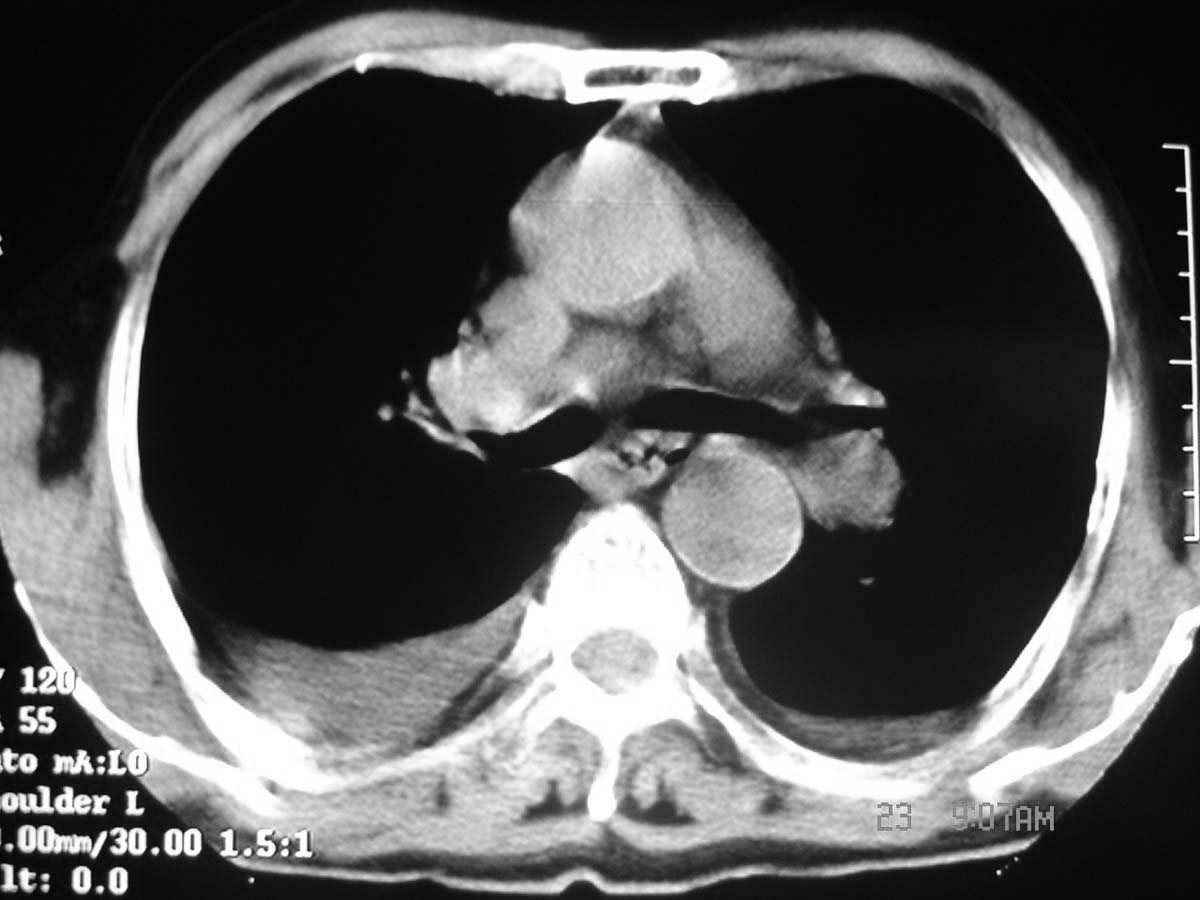

以下是引用守望可可西里在2006-11-23 14:33:00的发言:[br][br] 糖尿病病人很容易继发结核,病人又有双侧胸膜增厚、粘连、胸腔积液以及双上肺的斑片状、条索状影结核病灶影,以一元论考虑,右下肺病变首先考虑干酪性肺炎,可以正规抗炎治疗后复查,排除一般的肺炎。